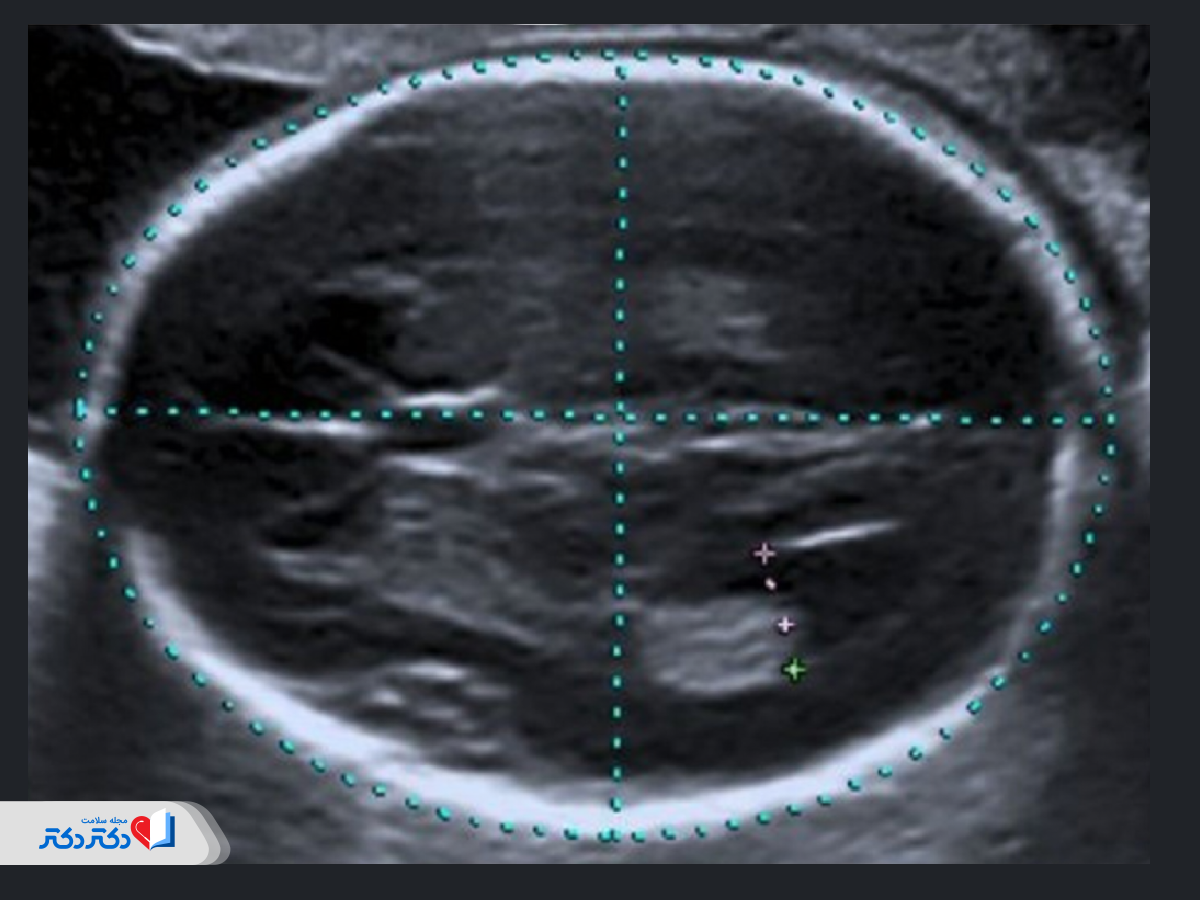

مغز

بررسی مغز در این سونوگرافی شامل موارد زیر است:

- ارزیابی فضاهای پُر از مایع داخل مغز و شکل مخچه؛

- تشخیص کیست در شبکه کوروئید (مجموعهای از عروق خونی و سلولهای اپاندیمال تولیدکننده مایع مغزی نخاعی).

کیستهای جنینی معمولا نشاندهنده افزایش خطر ناهنجاریهای کروموزومی هستند؛ اما خوشبختانه اکثر این کیستها تا هفته ۲۸ بارداری و بدون ایجاد تاثیر منفی روی جنین از بین خواهند رفت.